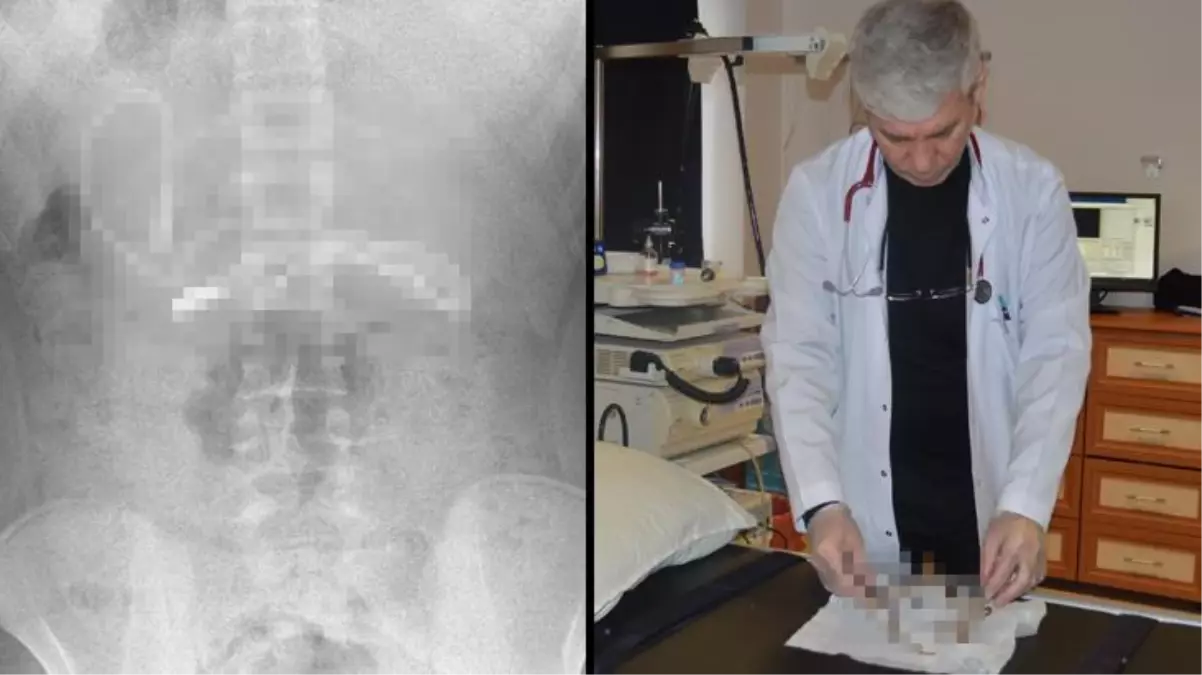

Diyarbakır'da kusma ve bulantı şikayetiyle hastaneye götürülen, çekilen röntgeninde 1 metrelik şarj kablosu ve toka yuttuğu tespit edilen 15 yaşındaki erkek çocuğu, Elazığ'da gerçekleştirilen operasyonla yuttuğu cisimlerden kurtuldu.

Diyarbakır'da kusma ve bulantı şikayetiyle ailesi tarafından hastaneye götürülen erkek çocuğunun çekilen röntgeninde, midesinde şarj kablosu ve toka olduğu tespit edildi. Bunun üzerine çocuk, ambulans ile Fırat Üniversitesi Hastanesi'ne sevk edildi. Üniversitenin Çocuk Gastroenteroloji Hepatoloji ve Beslenme Bilim Dalı Başkanı Prof. Dr. Yaşar Doğan ve ekibi tarafından yapılan endoskopik işlemle çocuğun midesindeki kablo ve toka başarıyla çıkarıldı. Tedavisinin ardından sağlığına kavuşan çocuk taburcu edildi.

Ameliyatı gerçekleştiren Prof. Dr. Yaşar Doğan, kablonun bir ucunun ince bağırsağa geçmesi nedeniyle zorlandıklarını ifade ederek, "Hastanın kusma ve karın ağrısı şikayetleri olması üzerine sağlık kuruluşuna başvurulmuş. Orada yapılan incelemelerde hastanın midesinde kablo tespit edilmesi üzerine bize danışıldı. 112 aracılığıyla hastaya gerekli işlemi yapıp yapmayacaklarını bize sordular. Biz de hastayı bize gönderebileceklerini kendilerine ilettik. Hasta bize geldikten sonra ön hazırlık yapıldı ve gerekli olan açlık süresinin ardından hastaya endoskopik işlem yapıldı. Endoskopik işlemle midedeki kablo çıkarıldı. Kabloyu çıkarırken açıkçası zorlandık, çünkü kablonun bir ucu ince bağırsağa geçmişti. İşlem başarılı bir şekilde sonlandırıldıktan sonra hasta sağlıklı bir şekilde evine gönderildi" dedi.